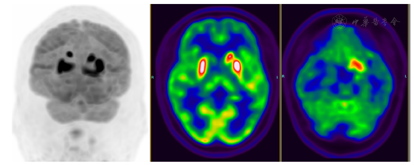

MRI:左侧基底节区及左侧海马在T2 Flair及DWI上见片状稍高信号,缺血性改变(图1)?18F-FDG PET/CT(发病20 d):双侧尾状核体部、左侧尾状核头、双侧壳核、左侧颞叶内侧(包括左侧海马-杏仁核复合体)、左侧额叶内侧及左侧岛叶代谢增高,全身未见明确恶性肿瘤征象(图2)。

据报道,超过95%的抗IgLON5抗体相关脑病患者的MRI表现不明显或非特异性,多为轻度至中度脑干、双侧海马和小脑萎缩,T2 Flair信号增高[1]。影像学上抗LGI1抗体脑炎主要表现在边缘系统,包括海马、杏仁核、颞叶、岛叶及扣带回皮质结构,基底节受累为不典型表现,MRI上为上述部位的T2WI及T2 Flair序列的高信号[7]。本例头颅MRI显像示左侧基底节区及左侧海马的T2 Flair及DWI信号略增高。国内一项研究从9个医疗中心招募了13例抗IgLON5抗体阳性的患者,其中4例接受18F-FDG PET检查,1例患者表现出双侧脑白质代谢下降,2例患者表现出颞叶代谢下降,1例患者表现出双侧额叶和双侧基底神经节的FDG代谢略有增加[3]。苏柳迪等[7]报道的5例LGI1抗体脑炎患者的18F-FDG PET/CT发现,3例为尾状核、海马及颞叶的代谢增高,1例颞叶的代谢减低,1例代谢未见异常。本例因CEA及非小细胞肺癌抗原稍升高,临床为排除肿瘤,行全身的PET/CT。18F-FDG PET/CT显示双侧尾状核体部、左侧尾状核头、双侧壳核、左侧颞叶内侧(包括左侧海马-杏仁核复合体)、左侧额叶内侧及左侧岛叶代谢增高,全身未见明确恶性肿瘤征象。18F-FDG PET/CT较MRI发现病变的范围更大且更明显,提示18F-FDG PET/CT在脑炎的敏感性更高。本例患者的MRI及18F-FDG PET/CT的表现均以基底节及边缘叶系统受累为主,其中边缘叶受累与典型的抗LGll抗体脑炎影像学改变相符。